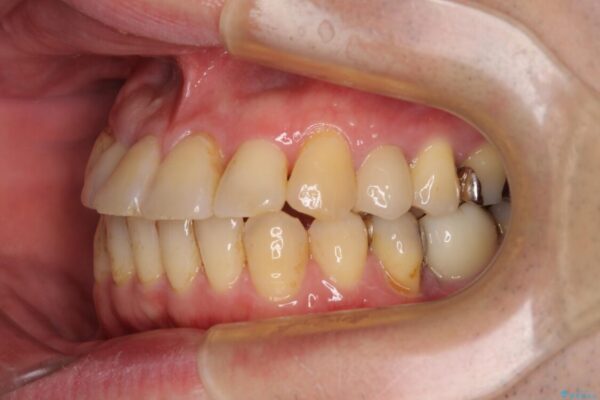

治療後

• 割れてしまった奥歯とデコボコの前歯 矯正治療とインプラント治療 治療後画像

治療後について

骨造成や歯肉移植など、治癒期間の長い処置を必要としたため治療期間は長くなりましたが、安定した咬み合わせと整った歯列となり、患者様には大変満足していただきました。